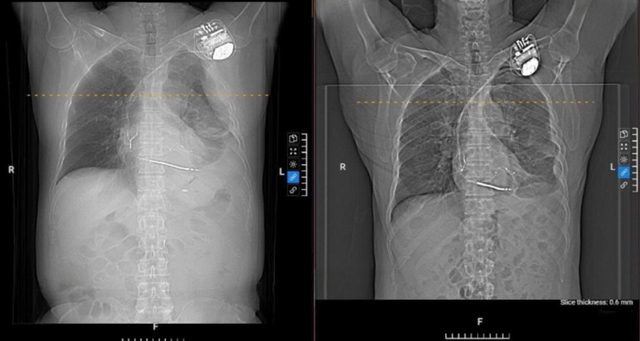

Bác sĩ Đặng Thị Mai Khuê, Phó trưởng khoa Nội tổng hợp, BVĐK Tâm Anh TP HCM cho biết: Kết quả chụp CT đa lát cắt cho thấy ông Pirone bị tràn dịch màng phổi bên trái, dịch khu trú từng ổ. Đây là tình trạng tích tụ dịch bất thường trong khoang màng phổi, nguyên nhân thường gặp là nhiễm trùng do viêm phổi, lao màng phổi, nhiễm vi khuẩn, virus, nấm.

Hình X-quang cho thấy tràn dịch màng phổi bên trái (trái) và sau điều trị (phải) của bệnh nhân. Ảnh: BVCC

Ông Pirone được chỉ định làm thêm xét nghiệm cấy đàm và PCR đa tác nhân, chọc dịch màng phổi xét nghiệm tế bào, sinh hóa, vi sinh. Kết quả xác định tràn dịch màng phổi là dịch viêm cấp tính, không tế bào ác tính – là biến chứng của viêm phổi, do vi khuẩn tụ cầu vàng gây ra.

Sau 20 ngày điều trị tích cực, tình trạng bệnh được cải thiện rõ rệt, dịch ở phổi được cải thiện nhiều, ông Pirone được xuất viện sau đó. Tái khám sau một tuần, người bệnh được siêu âm, chụp X-quang kiểm tra lại, lượng dịch cải thiện gần như hoàn toàn, không còn triệu chứng đau tức ngực, khò khè, hết ho đàm.